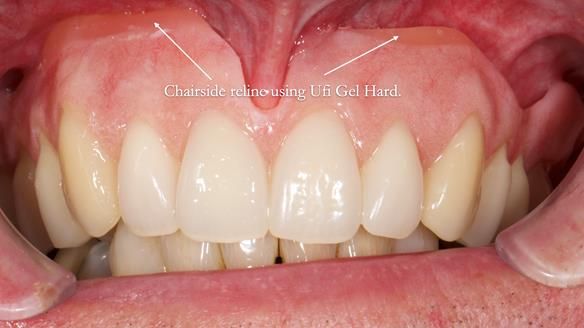

Two months later, after careful discussion with Jeremy, I decided to revise the plan:

We sacrificed the upper canine roots and made a Mk2 temporary complete denture to provide more tongue space and improve speech.

Three months after fitting, a reline was carried out to adapt to tissue changes from the canine and molar extractions.